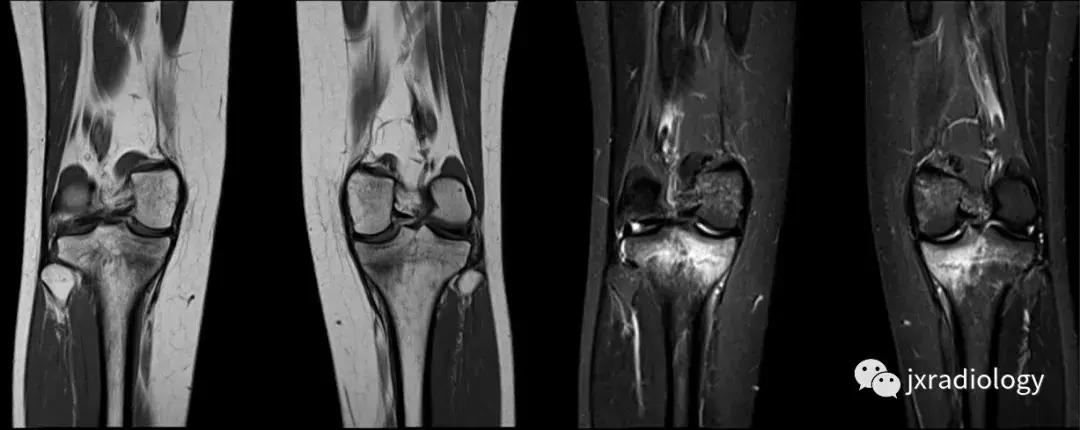

图2:骨性关节炎(OA):男,58岁,股骨内侧髁负重区有软骨缺损,伴有边缘小骨赘和继发性软骨下骨髓水肿。骨性关节炎通常不与创伤性病因分类,而是作为退行性病变分类(a:冠状T1-WI; b:冠状PDWI-FS; c:矢状PDWI-FS)。

图3:应力(疲劳)骨折:女,25岁,最近在没有适当热身的情况下在健身房参与剧烈运动的冠状位T1WI和STIR图像。她主诉出现双侧内侧胫骨疼痛。在双侧胫骨中,内侧近端应力性骨折是明显的。

图4:SIF(软骨下不全性骨折):在过去,每当在股骨内侧髁上观察到这种软骨下病变时,它就被标记为膝关节自发性骨坏死(SONK)。现在它被认为是一个不全性骨折。这些不全性骨折通常发生在股骨内侧髁和股骨头,并存在于老年人中(它们与骨质疏松症和生物力学改变相关,如在不稳定的半月板损伤中。与其他应力性骨折类似,低信号的骨折线在水敏性序列(a,b:冠状和矢状PDWI-FS)上被高信号的骨髓水肿包围。

图5:长期的SIF(软骨下不全性骨折)伴股骨外侧髁软骨下塌陷、大面积水肿(不如上图中显示的内侧髁位置常见)。

图6:内侧胫骨平台上不常见的SIF(软骨下不全性骨折)(a,b:矢状和冠状PDWI-FS)。